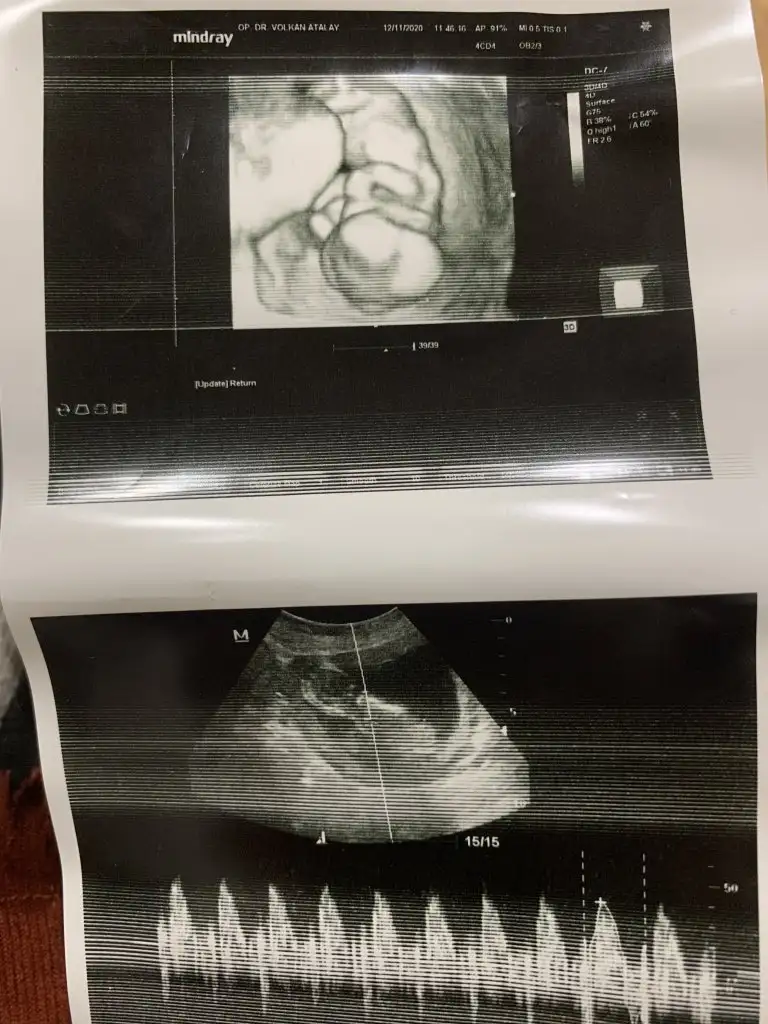

Kız bebeğinizKıza benzettim dedi doktor ama bacak arasi göremedik hala 15. Haftamdayim

Kız gibi sankiBenim cinsiyet icin doktor %80 lik bir sey soyledi ama degisir mi diye biraz endise ediyorum. Sizin tahmininiz nedir

Kız gibi sanki

Kizdir o zamanEveet doktorda oyle soyledi yuzde 80 kiz dedi